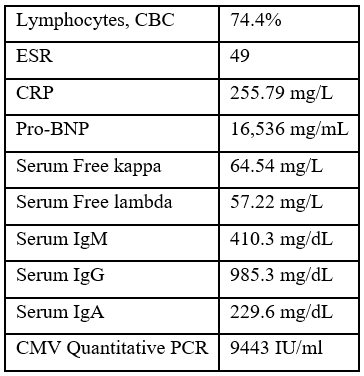

Table 1

Figure 1: CT chest showing large pericardial effusion.